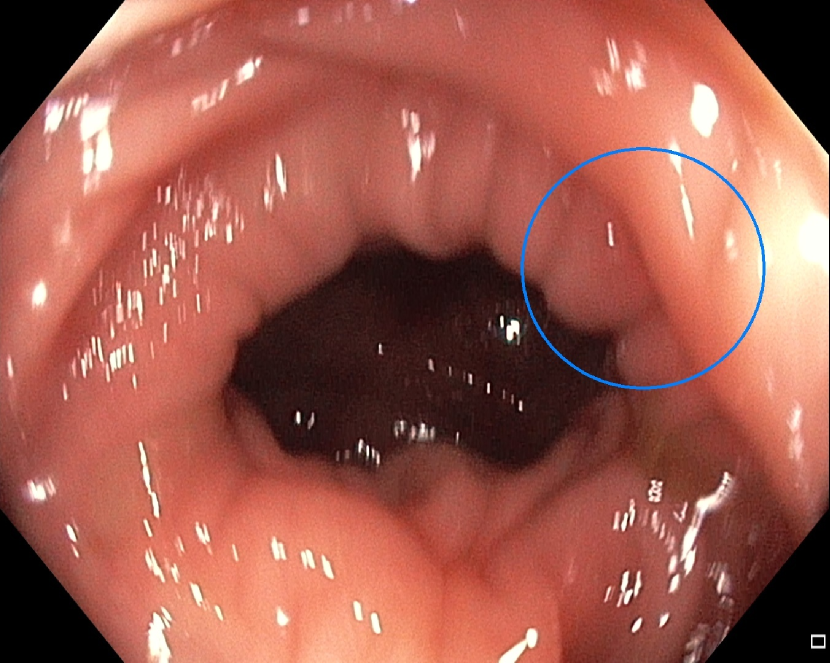

(h)

Figure 7: Sample images from the testing dataset, with results from the best performing model. White boxes are the ground truth annotations, blue ellipses are the model predictions. In the first row, examples of false negative polyps are shown: (7(a)) a small and distant polyp, (7(b)) a polyp partially covered by water/bubbles, (7(c)) a polyp framed in blue light, (7(d)) a large polyp near the image boundary and overexposed. In the second row, examples of false positive detections are shown: (7(e)) the model activates on a artifact due to stain and motion blur, (7(f)) the model activates on a solid residue, (7(g)) the model activates on an area of the colonic mucosa that is not well inflated, (7(h)) the model activates on a dark and distant area of the colonic mucosa whose shape is similar to a polyp.

Finally, in Figure 7, we display examples of false negatives and false positives from the test set, generated by the best performing model. To visually assess the performance on a whole video, we have uploaded a 60-minute colonoscopy video featuring 6 polyps, the longest in our test set, at https://figshare.com/s/fbb0834a21082984336c (with predictions marked in cyan and ground truth boxes in white). The image examples illustrate how the model struggles with small, occluded, or poorly imaged polyps, and generates false positives in areas that visually resemble polyps, often due to motion or suboptimal imaging. These observations persist throughout the entire video analysis, highlighting the importance of minimizing false positives throughout the entire procedure while maintaining high polyp recall.